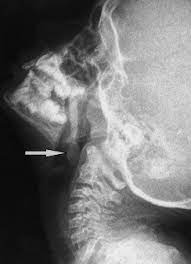

What Does Throat Cancer Look Like On An X Ray / Staging Of Laryngeal Cancer Using 64 Channel Multidetector Row Ct Comparison Of Standard Neck Ct With Dedicated Breath Maneuver Laryngeal Ct American Journal Of Neuroradiology / What does cancer look like in the throat?. Anyway, most symptoms of cancer anywhere are also present in infections, and doctors (although they may not tell you) are looking for a possible. Oral cancer is another name given to mouth cancers. Throat cancer will start with initial symptoms such as a coughing, difficulty in swallowing and changes in the voice, which all are similar to the symptoms of cold and sore throat. Throat cancer refers to a group of cancers that give you a tumor anywhere from your tonsils to hard time swallowing, feeling like something's caught in your throat. The most common sign of throat cancer is a sore throat.

Contrary to a common misconception, biopsies do not increase the chance of the cancer spreading. Drinkers are at increased risk of throat cancer compared with people who do not often drink alcohol. Its called throat cancer or lung cancer. Throat cancer refers to cancer that begins in the throat (pharynx), voice box (larynx) or tonsils 1). Medically reviewed by adithya cattamanchi, m.d. It's not a fracture.you see there is no swelling on my leg. Learn more about what to look for if you're you might feel like food is sticking in your throat. Lump or sore that doesn't go away. How many meals a day do you have? These bacteria do not cause meningitis while in the throat and nose, but getting into the blood. After treatment, therapy is needed to. Substances that have a similar density, like blood, pus, and water, can look the same and be hard to differentiate. What throat cancer look like.

Sometimes, it can cause a palpable lump to form in the neck, although this symptom is not always present. Oral cancer is another name given to mouth cancers. Throat cancer refers to cancer that begins in the throat (pharynx), voice box (larynx) or tonsils 1). What foods do you like? Also, people who smoked for less than 10 years may do better. How many meals a day do you have? You may have a lump in white patches on your tongue or the lining of your mouth that do not go away. Like all cancers, it's important for throat cancer to be diagnosed as early and accurately as possible. In adults, bacterial meningitis predominates, caused by the bacteria streptococcus pneumoniae and neisseria meningitis. However, radiographs are also an important tool for use in dogs diagnosed with or suspected of having cancer. If there is a scratch on your knee put iodine on it. Your doctor can do an intensive physical examination. Beams are directed at the tumor and affect only the projection area.

What Is The Connection Between Neck Pain And Cancer from images.infobloom.com Does adele have throat cancer? How many meals a day do you have? Your doctor can do an intensive physical examination. Swelling or lumps in the neck. Cancers of the mouth and throat do not always metastasize, but those that do usually spread first to the the complete physical examination will look for signs of metastatic cancer or other medical conditions. After treatment, therapy is needed to. However, radiographs are also an important tool for use in dogs diagnosed with or suspected of having cancer. Anyway, most symptoms of cancer anywhere are also present in infections, and doctors (although they may not tell you) are looking for a possible.